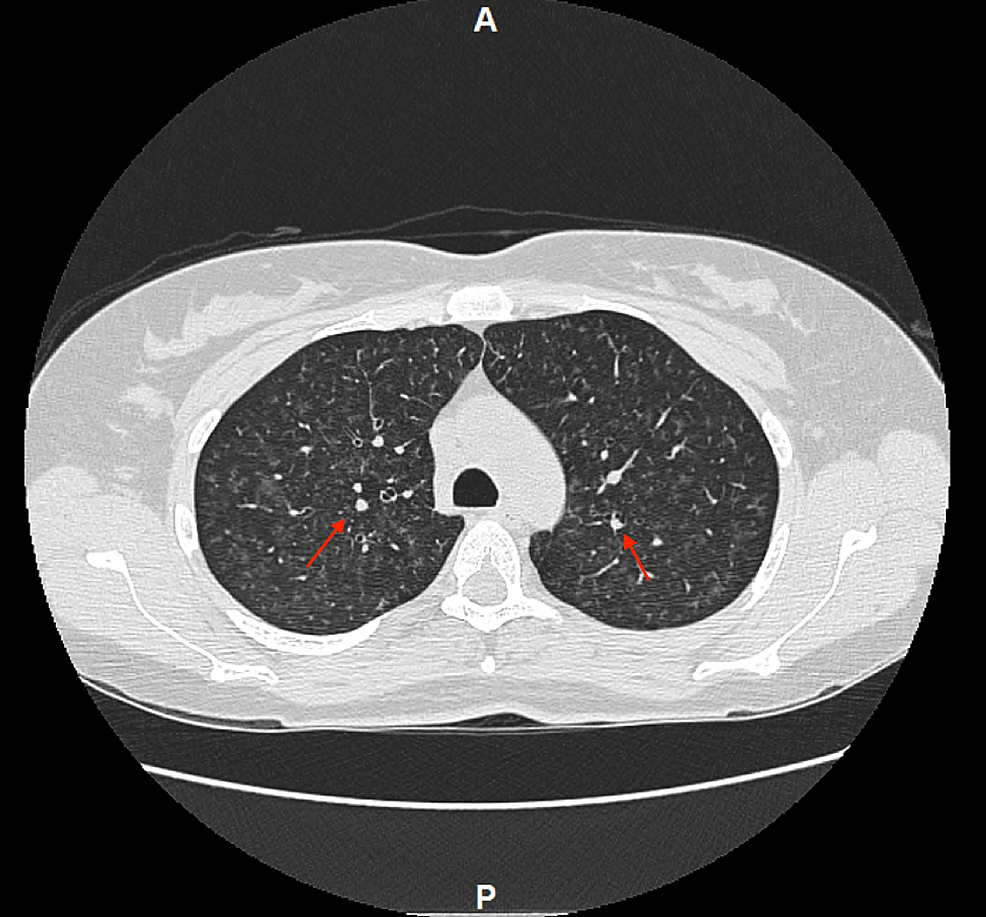

TreeInBud Pattern AJR